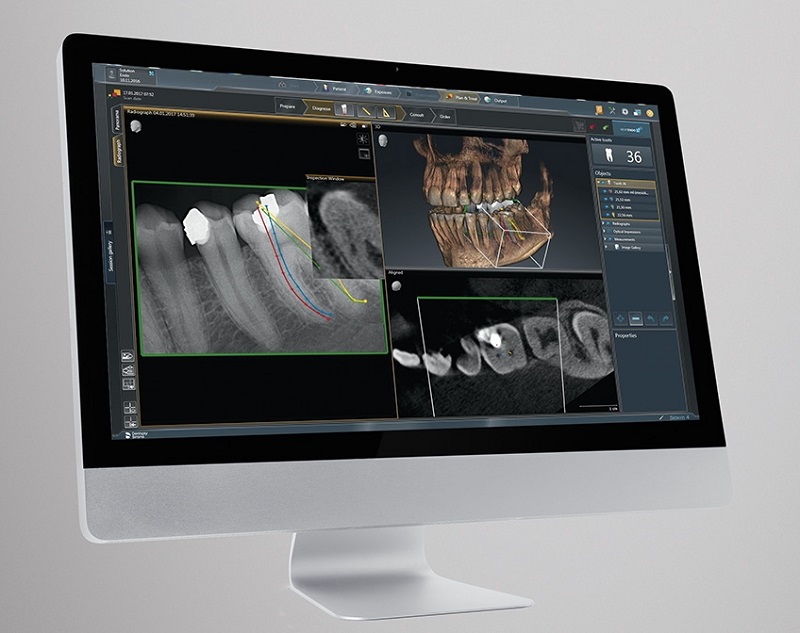

- CAD/CAM tehnologija

- 3D dijagnostika - digitalni ortopan

- Radiologija

- Orthophos SL 3D